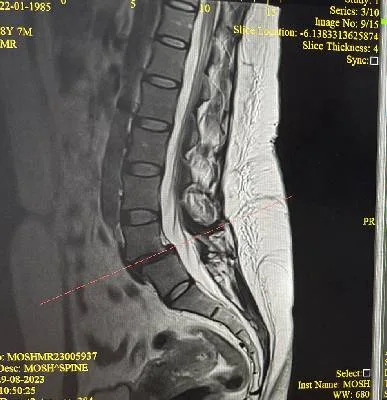

Dr. Haytham Elkhatib is a distinguished orthopaedic surgeon specializing in comprehensive musculoskeletal care. With expertise in trauma, fracture treatment, and advanced interventional joint injections, he offers innovative solutions for various conditions.